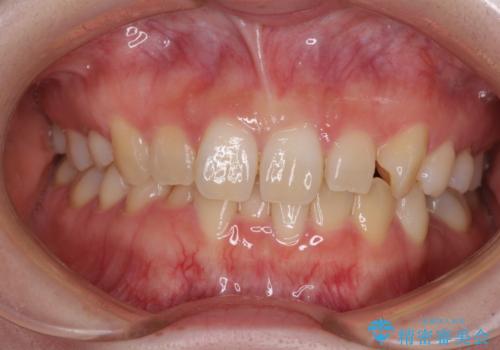

ディープバイトをインビザライン矯正で改善

前歯のインプラント治療 折角なので矯正治療できれいな歯並びに

八重歯を抜歯矯正でスッキリと メタルブラケットでの矯正治療

前歯のクロスバイト ワイヤー装置を併用したインビザライン矯正

八重歯と開咬を治したい 目立たないハーフリンガル矯正

前歯のクロスバイトを短期間で解消 目立たないワイヤー矯正

前歯のがたつき 部分矯正でコストダウンしながら、かみ合わせも治療

【引っ込んだ前歯が気になる、真ん中の線も揃えたい】インビザライン症例

【出っ歯が気になる】インビザライン症例

【前歯のガタガタが気になる】インビザライン症例

八重歯で口元が膨れている ワイヤー装置での抜歯矯正

【モニター】飛び出した上顎前歯のワイヤー矯正で改善

前歯が反対に咬んでいる インビザラインによる矯正治療

重度のガタガタと出っ歯をワイヤーによる抜歯矯正で整った歯並びへ

八重歯をインビザラインで非抜歯矯正